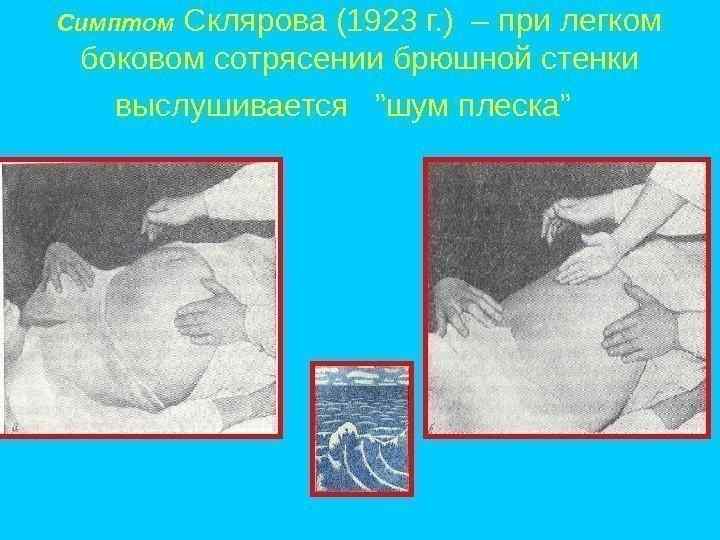

Клиническая картина Основные симптомы: Боль без четкой локализации, схваткообразная или постоянная с разной степенью интенсивности. симптом Тэвенара – боль при пальпации на 2 поперечных пальца ниже пупка(проекция корня брыжейки тонкой кишки). При странгуляционной непроходимости. вздутие живота – может быть симметричным и ассиметричным(странгуляционная). Характерно для высокой непроходимости. видимая перистальтика – характерна для механической непроходимости. Рвота – многократная, ненадолго приносящая облегчение, переходящая постепенно в каловую рвоту. симптом Валя – высокий тимпанит над проекцией толстой кишки – характерно для ранней механической непроходимости. симптом Шимана – западение живота в левой подвздошной области, в то время как в правом подреберье вздутие толстого кишечника, при завороте сигмовидной кишки. симптом Склярова – шум плеска при сукуссии. симптом Спасокукоцкого Вильмса – шум падающей капли, растянутые петли кишечника. Аускультация живота, по образному выражению наших хирургических учителей, необходима для того, чтобы «услышать шум начала и тишину конца» (Г. Мондор). «гробовая тишина» отсутствие перистальтики. пальцевое ректальное исследование – «каловый завал» , вздутие ампулы. интоксикационный синдром – температура, тахикардия, головная боль и слабость – признак калового застоя.